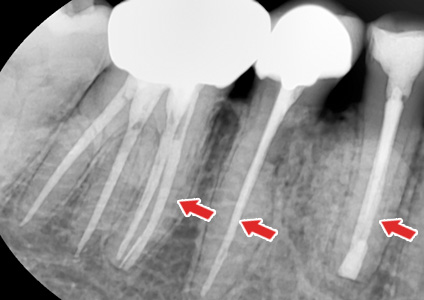

½Å°æÄ¡·á¸¦ ÇÑ Ä¡¾ÆÀÇ X-ray »çÁø